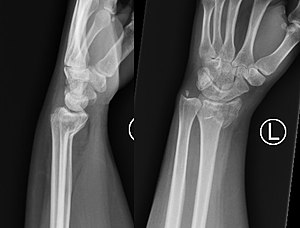

손목관절 중에서 골절이 많이 일어나는 골절이 노뼈(척골)의 골절이 많이 일어나는데,

어떻게 골절이 되느냐에 따라서 Colles 골절, Smith 골절로 지는데

Smith 골절일 경우 주로 시행한다고 한다

사진 삭제

사진 설명을 입력하세요.

Xray상으로도 보이는 손목이 완전 절반쩍도 꺽이면서 발생한 골절은 스미스 골절이라고 하는데

손목 구조상 손목을 관적을 틀면 손등까지 움직이므로 보통 슈가 스프린트를 사용한다,